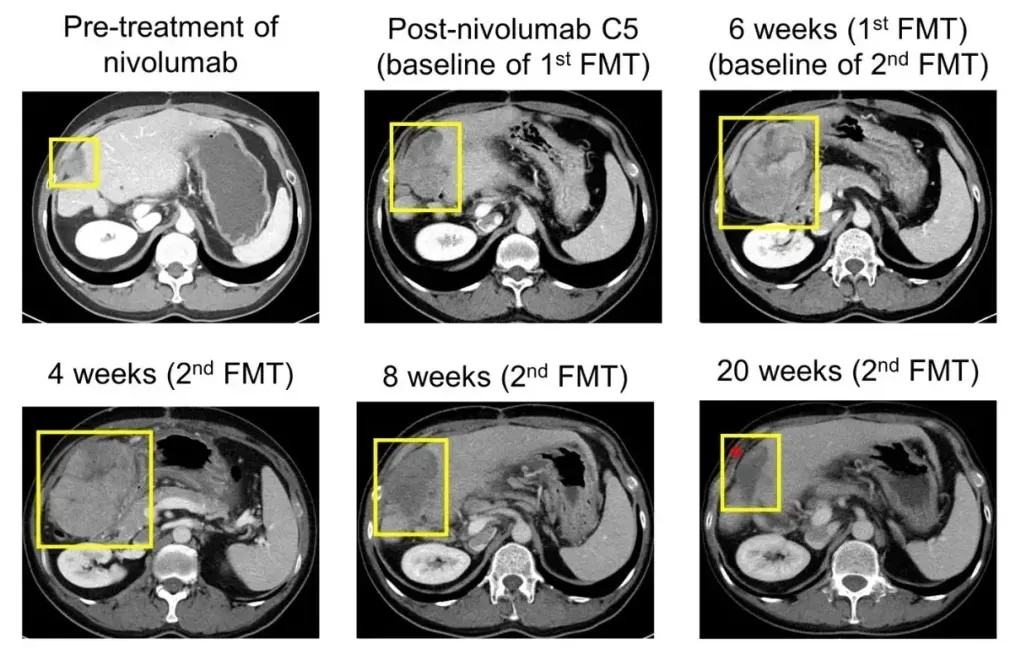

临床研究(NCT04264975,FMT治疗晚期难治性胃肠道肿瘤)为肝癌患者带来突破:一例纳武单抗耐药的转移性肝癌(HCC)患者(R7),经持续免疫治疗联合粪便微生物移植(FMT)治疗后,疗效显著:肿瘤逐步缩小,第2次FMT治疗8周后缩小30.5%,后续进一步缩小至47.7%,最终实现部分缓解(PR,详见下图);同期血清甲胎蛋白(AFP)、PIVKA-II(拮抗剂Ⅱ诱导蛋白)显著下降。

▲图源“Cell Host Microbe”,版权归原作者所有,如无意中侵犯了知识产权,请联系我们删除